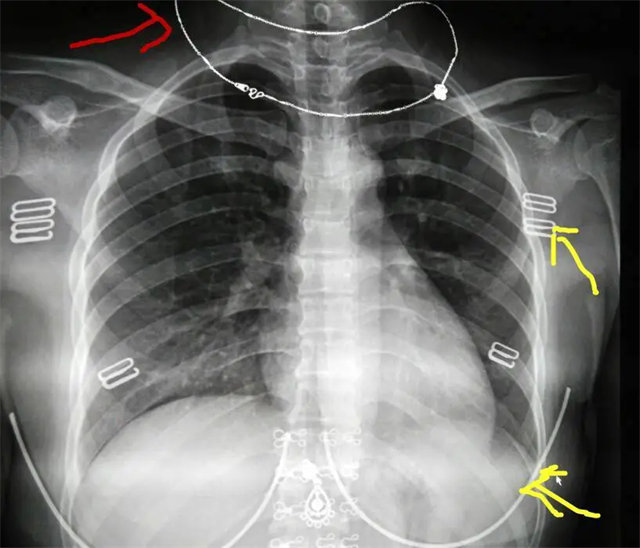

缺陷:肩胛骨未完全拉離肺野,吸氣不完全,存在金屬偽影遮擋,略有聳肩,且肺尖顯示不好,圖像顆粒感較強(qiáng),管電流量不夠,信噪比偏低。

解決:去除金屬物品后,按標(biāo)準(zhǔn)體位,使患者雙肩旋前與前胸一并緊貼成像件,適當(dāng)調(diào)高mAs,然后深吸氣后屏氣曝光。